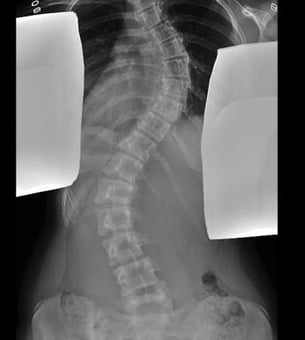

Children’s National Hospital has a team of highly-specialized experts that work together to correct idiopathic scoliosis in adolescents using posterior spinal fusion surgery. Children with idiopathic scoliosis have an abnormal curve in their spine and may show the following signs:

Posterior spinal fusion is the surgical process of straightening the spine and preventing the curve from getting worse. Metal implants are used to hold the spine in a straighter position until the bones fuse together.